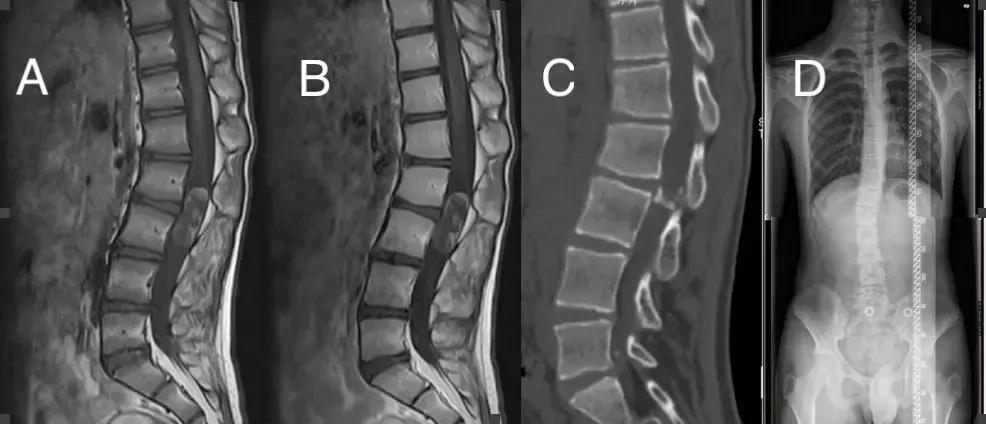

腰椎增强MRI提示:腰2-3椎体水平椎管内见椭圆形病灶,大小约40*15mm,以长T1长T2信号为主,内信号不均,见稍短T1稍短T2信号,增强扫描未见确切强化。CT示:腰2-3椎体水平椎管内见椭圆形大小约40*15mm低密度影,内密度不均,病灶内及边缘见弧形及斑点状钙化。全脊柱摄片提示:脊柱胸段向左侧凸,腰段向右侧凸。Cobb角为14°(图1)。

图1. A:MRI T1序列, B:MRI T1增强序列, C:CT矢状位,D:全脊柱摄片。